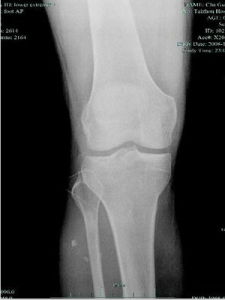

脛骨平台骨折傷後膝關節腫脹疼痛,活動障礙,因系關節內骨折均有關節內積血,應注意詢問受傷史,是外翻或內翻損傷,注意檢查有無側副韌帶損傷。關節穩定性檢查常受到疼痛、肌肉緊張的限制特別健康搜尋是在雙髁粉碎骨折者。在單髁骨折者,其側副韌帶損傷在對側該側副韌帶的壓痛點,即為其損傷的部位,在斷裂者,側方穩定性試驗為陽性清晰的膝正側位X線片,可顯示骨折情況,特別對於無移位骨折。